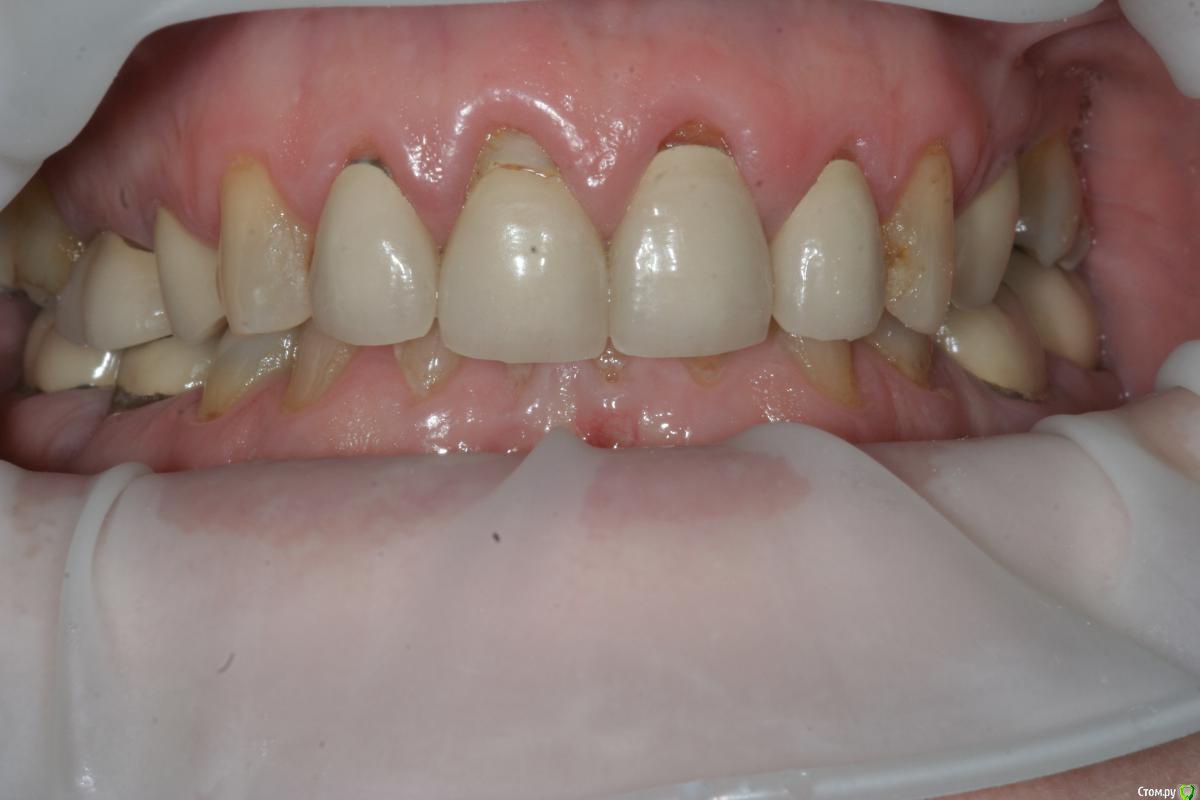

togrul Опубликовано 17 марта, 2015 Поделиться Опубликовано 17 марта, 2015 Добрый день коллеги. Обратилась пациентка с просьбой заменить все реставрации + привести эстетически все в порядок.С чего бы вы начали? есть модели загипсованные в ЦС. Снимок КТ. Ссылка на комментарий

Rash163 Опубликовано 17 марта, 2015 Поделиться Опубликовано 17 марта, 2015 Я промерил бы глубину карманов.что там как. По снимку не очень видно. Определился с размерами фронтальных зубов, воск или дсд. 11,21 кажется висят относительно других.после этого будет понятно что делать. Пломбу на 11 убрать бы, десне очень плохо около нее. Ссылка на комментарий

togrul Опубликовано 18 марта, 2015 Автор Поделиться Опубликовано 18 марта, 2015 Вот еще фото лица. По бюджету нет ограничений ( мк на золоте, Емах). Провести снятие, эндо, воск, временные, перио нужно , но хирург не планирует ( по определенным причинам). Если делать перио во фронте какая методика было бы наиболее оптимальным в данной ситуации?Начал снимать коронки им 20 лет, под ними все очень даже не плохо) высота нижнего отдела лица снижена на сколько пока не готов ответить. модели будут Ссылка на комментарий

Doc.IQ Опубликовано 6 сентября, 2015 Поделиться Опубликовано 6 сентября, 2015 Я так понимаю что кейс завершен..хотелось бы услышать приведенный в исполнение план..хоть и фото мало,но по не у видно,что работа очень хороша..покрайней мере фронт выглядит симпотно..Даже разные зениты двоек придают индивидуальности и живость..хотя некоторые и не согласятся со мной и скорее всего взяли бы в руки скальпель Ссылка на комментарий

togrul Опубликовано 6 сентября, 2015 Автор Поделиться Опубликовано 6 сентября, 2015 Я так понимаю что кейс завершен..хотелось бы услышать приведенный в исполнение план..хоть и фото мало,но по не у видно,что работа очень хороша..покрайней мере фронт выглядит симпотно..Даже разные зениты двоек придают индивидуальности и живость..хотя некоторые и не согласятся со мной и скорее всего взяли бы в руки скальпель Все верно кейс закончен)Мы согласовали вакс ап , перенесли в полость рта согласовали форму и размер передних зубов, не много переделали восковку. По силиконовым ключам отпрепарировали зубы и где то около 1,5 носили временные коронки и параллельно начали постоянную работу. Везде Емах одиночки, кроме 2 сегмента ,там поставили мост из 3 х ед. Место не было для имплантации + нужен был синус,подумали и решили сделать мост. Никакой хирургии не было только эндо.Фото будут Ссылка на комментарий